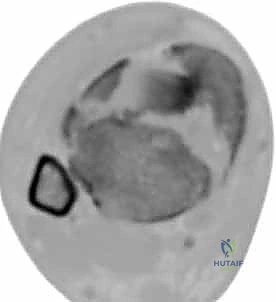

2. التصوير المقطعي المحوسب (CT Scan) - المعيار الذهبي

لا يمكن إجراء جراحة حديثة لكسر البيلون دون إجراء أشعة مقطعية. لماذا؟

كشفت الأبحاث المتقدمة (مثل أبحاث كول Cole وزملائه) والتي يعتمد عليها الدكتور هطيف، أن الأشعة المقطعية، وخاصة مع إعادة البناء ثلاثي الأبعاد (3D Reconstruction)، تسمح برسم خريطة دقيقة لكل قطعة عظمية مفتتة في السطح المفصلي (AO/OTA 43-C3).

تظهر الأشعة المقطعية النمط الثابت لتفتت البيلون والذي يتكون عادة من ثلاث قطع رئيسية:

* القطعة الأمامية الجانبية (Chaput fragment): متصلة بالرباط الظنبوبي الشظوي الأمامي.

* القطعة الخلفية (Volkmann fragment): متصلة بالرباط الظنبوبي الشظوي الخلفي.

* القطعة الأنسية (Medial Malleolus): متصلة بالرباط الدالي.

وفي الوسط، توجد منطقة "الانهيار المفصلي" (Die-punch fragment) التي تُدفع داخل العظم.

يستخدم الأستاذ الدكتور محمد هطيف هذه الخريطة المقطعية لتحديد مسار الشقوق الجراحية، واختيار أحجام وأنواع الشرائح المعدنية المطلوبة، وتحديد تسلسل إرجاع القطع العظمية قبل دخول غرفة العمليات.